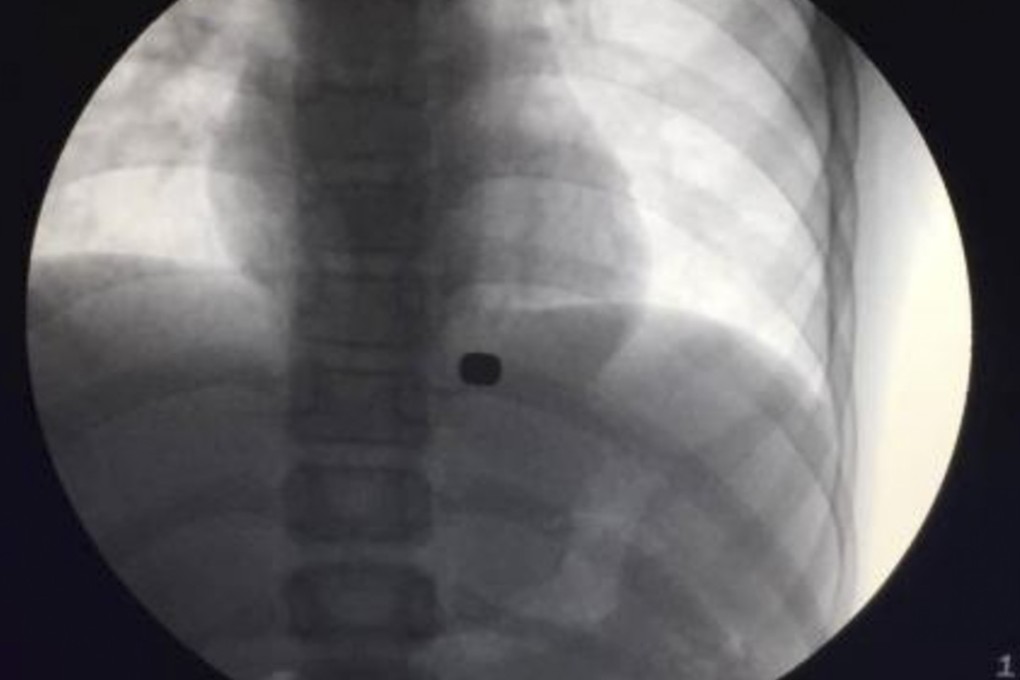

Hu and his team had tried to remove the button-sized magnets using an endoscopy, which is usually used to conduct internal examinations, but they found they were covered by tissues at the bottom of the boy’s stomach.

However. by attaching the powerful magnet to the endoscopy they were able to get round the problem.

Hu told the newspaper that without the magnets doctors would have had to dig a hole in the boy’s stomach.

“Even with open-chest surgery, it would be hard to find the magnets without tearing the tissue apart.”